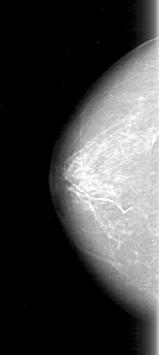

D_4097_1.LEFT_MLO

LEFT_MLO LINES 5311 PIXELS_PER_LINE 2446 BITS_PER_PIXEL 12 RESOLUTION 43.5 OVERLAY